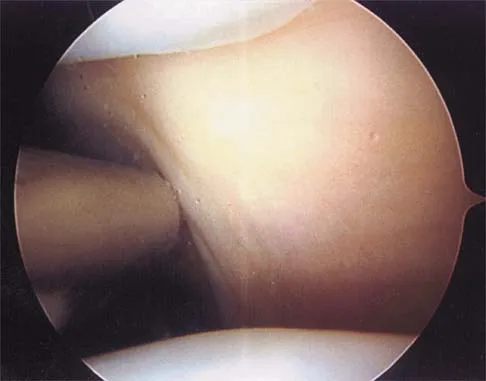

In the arthroscopic photograph shown in Figure 5, the structure labeled "A" functions primarily as a restraint to translation of the humeral head in what direction?

Explanation

The superior glenohumeral ligament identified as "A" in the figure functions primarily as a restraint to inferior glenohumeral translation of the adducted arm. The middle glenohumeral ligament is highly variable and pooly defined in up to 40% of the population and functions to restrain anterior translation of the externally rotated arm in the midrange of abduction. The anterior band of the inferior glenohumeral ligament is the primary restraint to anterior/inferior translation of the head with the shoulder abducted to 90 degrees and in maximum external rotation. Ticker JB, Bigliani LU, Soslowskiy LJ, et al: Inferior glenohumeral ligament: Geometric and strain-rate dependent properties. J Shoulder Elbow Surg 1996;5:269-279.

References:

- Owen MD, Kregel KC, Wall PT, Gisolfi CV: Effects of ingesting carbohydrate beverages during exercise in the heat. Med Sci Sports Exerc 1986;18:568-575.